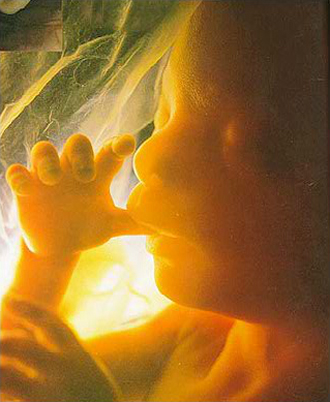

- 필수 검사

- 복부 초음파 (1회/4주)

- 기형아 검사 (통합검사/쿼드 혈액검사)

- 선택 검사 (16주~20주)

- 양수검사 (분만시 연령이 만 35세 이상, 기형 가족력이 있는 경우는 필수)